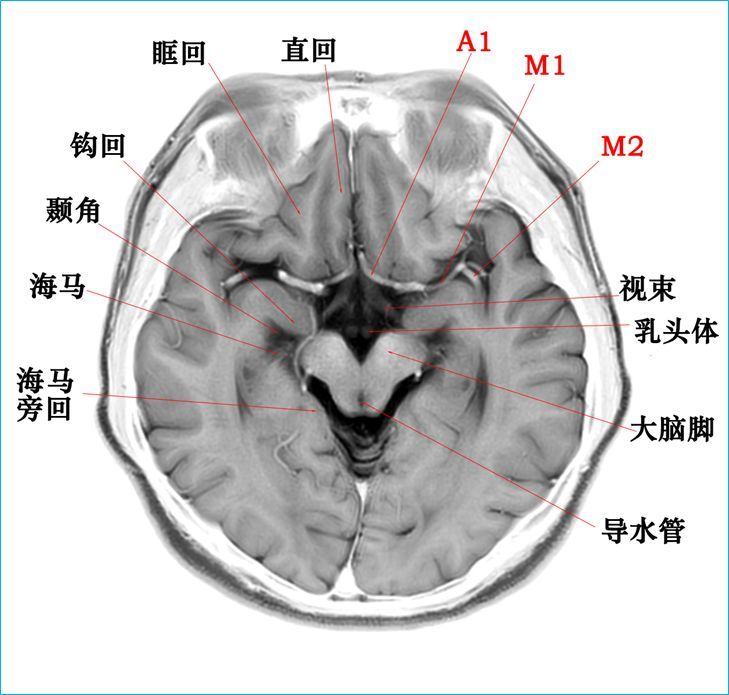

头颅mr横断面解剖中英文对照版,音乐 影像 解剖原来是另一番新天地

颅脑mr阅片手绘二徐桂兴博士

超棒颅脑mr阅片手绘版来啦

脑干:延髓,脑桥,中脑海马脑叶,基底节区额下回,颞

影像必备高清颅脑mr断层解剖图谱